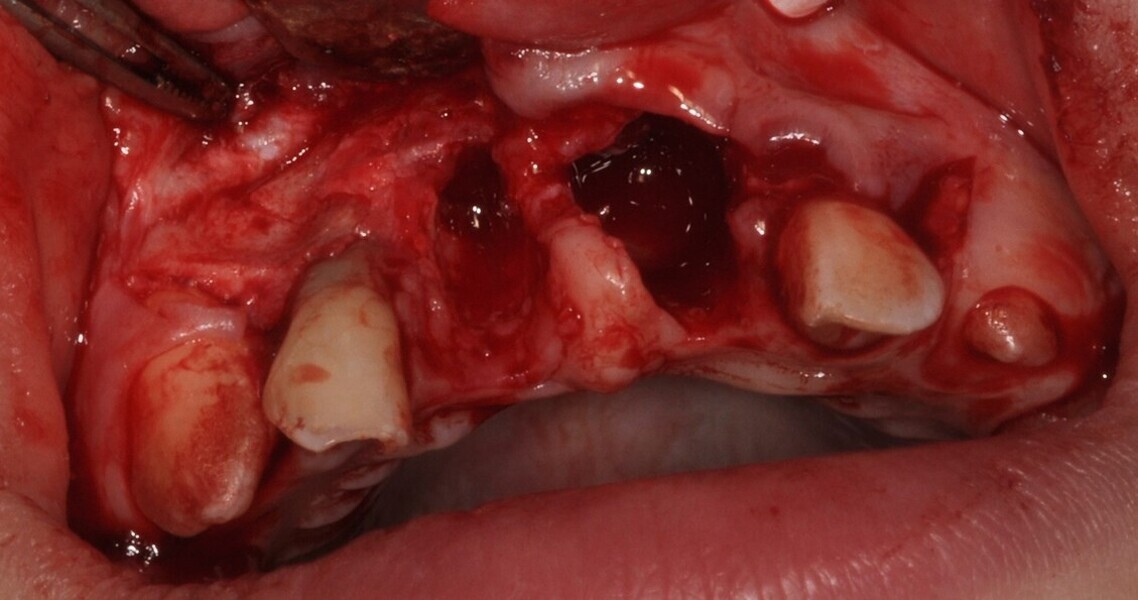

Ryc. 4¬_Stan miejscowy po ekstrakcji i ablacji kości.